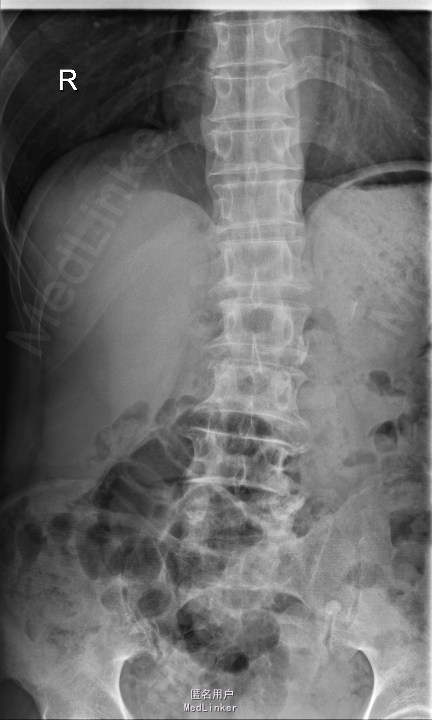

腰痛5年,加重伴左下肢放射性疼痛半个月 患者5年前无明显诱因出现腰痛,不伴下肢放射性疼痛、麻木、无力,腰部活动受限,劳累后加重,平卧休息可缓解。半个月前无明显诱因出现腰痛加重,伴左下肢放射性疼痛、麻木,腰腿活动受限,无低热、盗汗,无纳差、消瘦。

查体:左侧小腿外侧、足背感觉减退,右侧正常,双侧屈髋、伸膝、踝背伸肌肌力5级,左侧踇背伸、跖屈肌肌力4级,右侧踇背伸、跖屈肌肌力4-5级,双侧巴氏征阴性,直腿抬高试验左侧30°阳性,右侧阴性。 辅助检查: X-ray:腰椎退行性变,腰椎节段性性不稳 MR:腰椎间盘突出,腰3/4,4/5,腰4/5节段明显

诊断:腰椎椎管狭窄 处理: 1、完善相关辅助检查,明确诊断,有无手术指证; 2、完善手术评估,有无手术禁忌,手术风险及并发症; 3、在全麻下行腰椎后路减压,腰3/4左侧椎板减压,腰4/5椎间Cage植骨融合内固定术